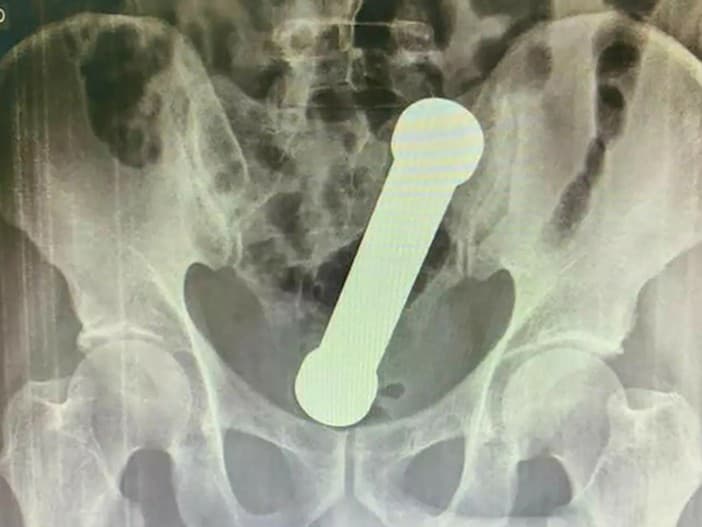

Po vyšetrení röntgenom bolo jasné, že predmet je uviaznutý na spojení hrubého čreva a konečníka a predstavuje riziko perforácie alebo iného vážneho poranenia. Najprv sa lekári pokúsili predmet odstrániť pinzetou, čo sa nepodarilo, a nakoniec musel chirurg zasiahnuť manuálne – do konečníka zasunul ruku až po predlaktie, aby činku bezpečne vytiahol.